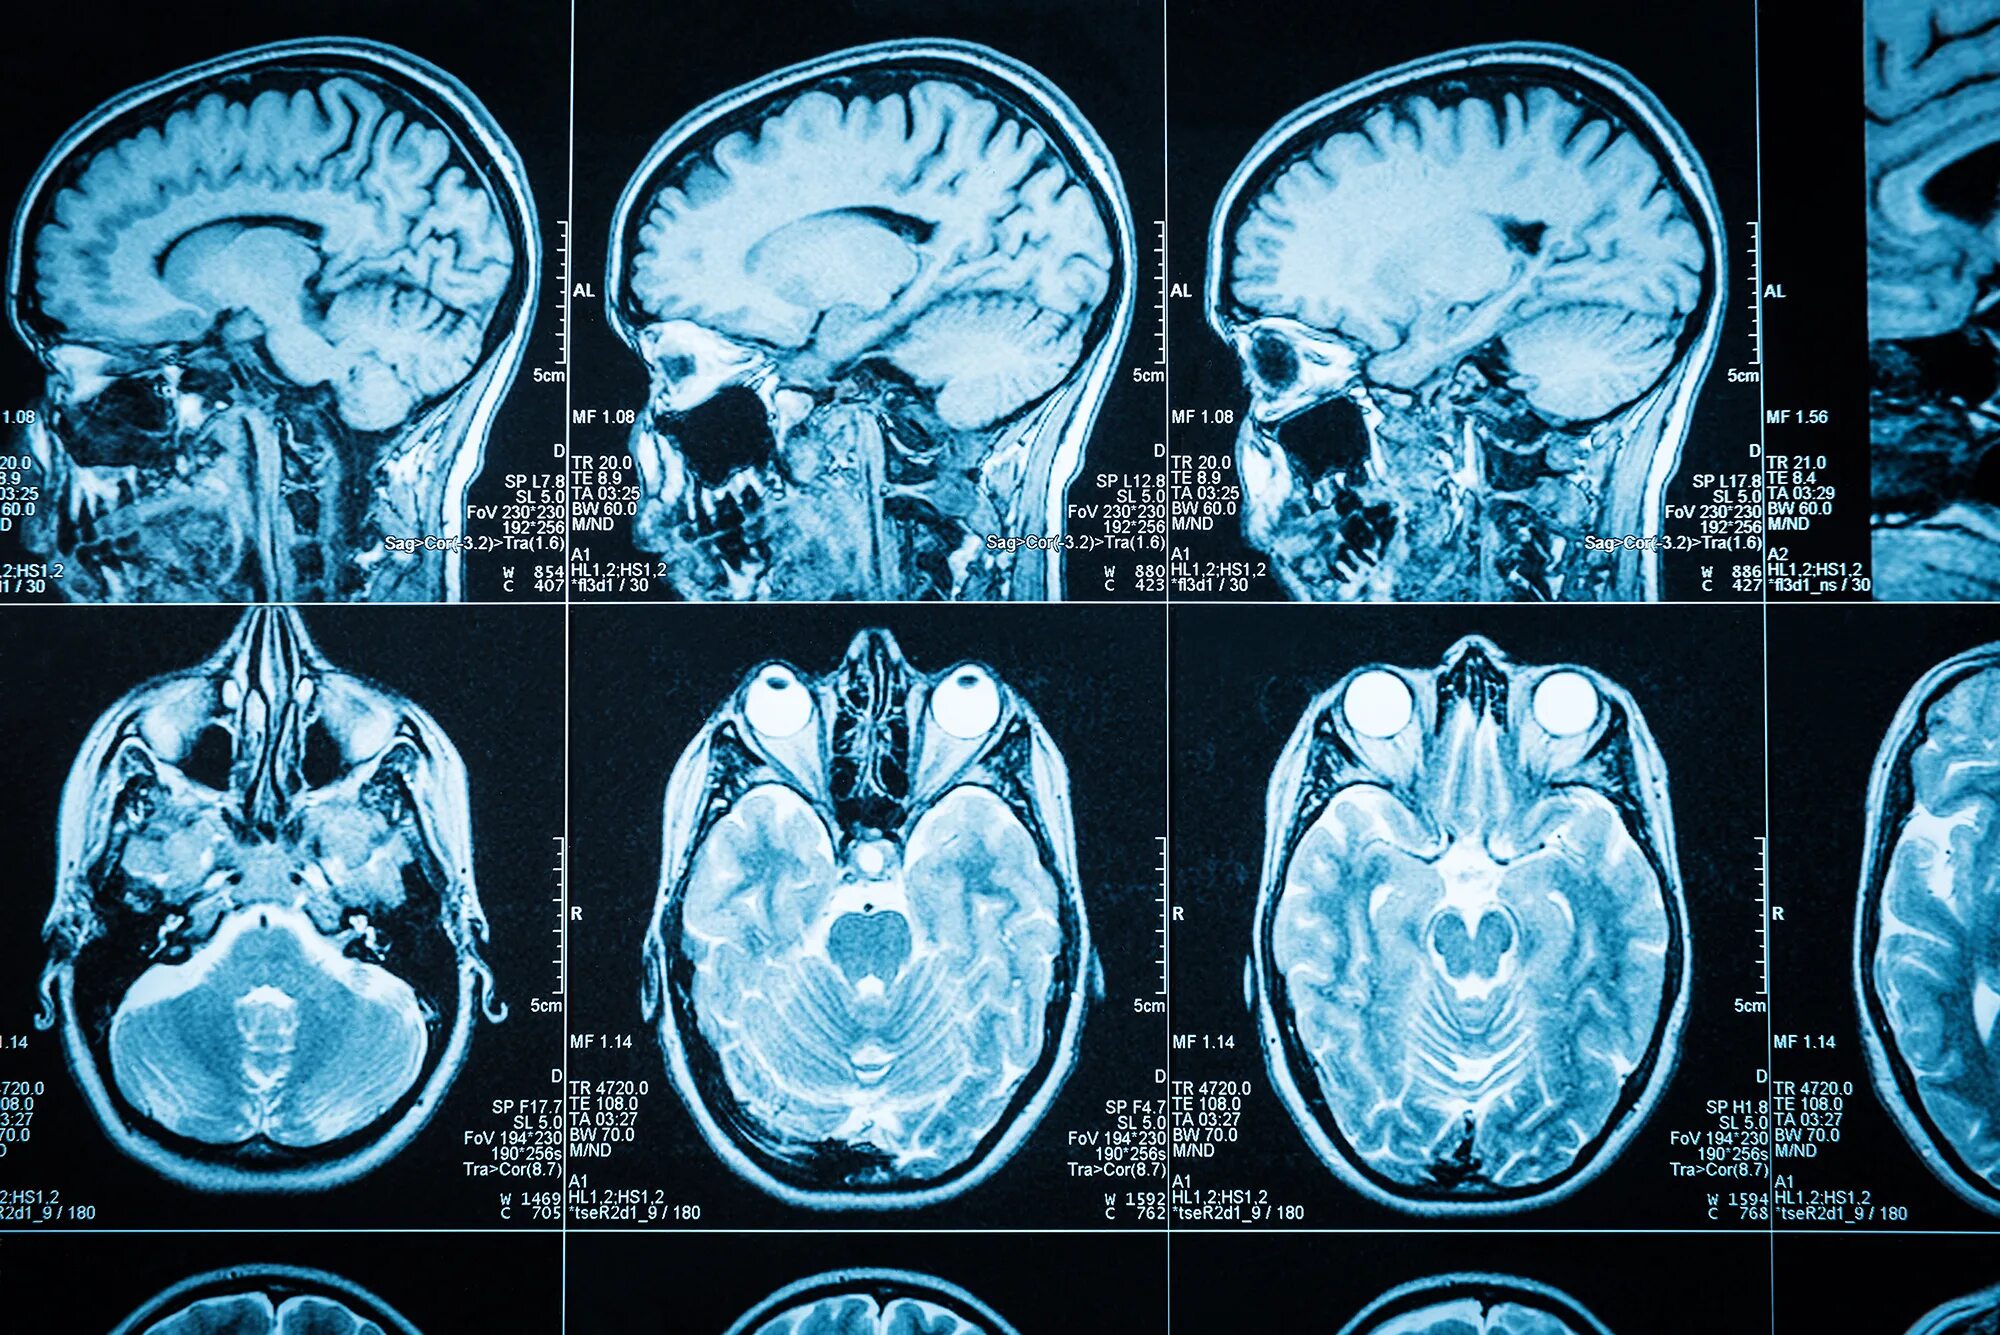

После мрт головного мозга